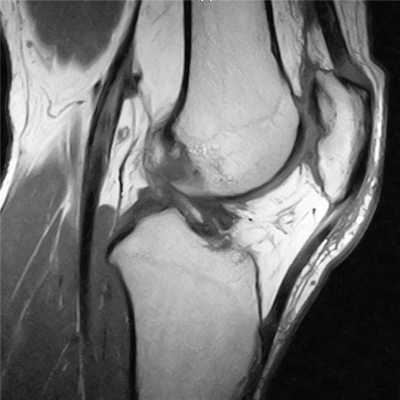

Пример расшифровки МРТ коленного сустава

На серии МРТ правого коленного сустава соотношения в суставе не нарушены.

Определяется скопление выпота в полости сустава и области околосуставных синовиальных сумок. Синовиальная оболочка с признаками.

Отмечается уплощение блока бедренной кости. Надколенник смещен кнаружи до 7мм, объем медиальной фасетки надколенника уменьшен. Костный контур надколенника в нижне-медиальных отделах деформирован, отмечается неоднородная структура суставного хряща надколенника в области медиальной фасетки за счет щелевидных дефектов, с фибрилляцией хряща на фоне субхондрального отека костного мозга в прилежащих отделах. Медиальный ретинакулум неоднородной структуры, в задних отделах разволокнен за счет разрыва его волокон. Целостность латерального ретинакулума не нарушена. Жировое тело Гоффа неоднородной структуры за счет участков отека. Связка надколенника локально неоднородной структуры на уровне прикрепления к надколеннику, с участками повышения интенсивности сигнала. Область бугристости большеберцовой кости не изменена.

Хрящевое покрытие мыщелков бедренной и большеберцовой костей неравномерно истончено, суставная полость сужена. Отмечается субкортикальный дефект в передненаружных отделах дистального эпиметафиза бедренной кости, участок кистовидной перестройки на фоне трабекулярного отека в прилежащих отделах. Определяются небольшие передне- и заднебоковые краевые костные разрастания мыщелков бедренной и большеберцовой костей.

Передняя крестообразная связка определяется на всем протяжении, утолщена, неоднородной структуры, контур связки четкий, общая целостность сохранена. Интенсивность МР-сигнала от задней крестообразной и коллатеральных связок не изменена, целостность их не нарушена.

Определяется повышение интенсивности МР-сигнала от латерального и медиального менисков, достоверно не распространяющееся на контур смежных суставных поверхностей.

В заднемедиальном отделе бедра, в области межмышечного пространства медиальной головки икроножной и полуперепончатой мышц, отмечается скопление жидкости.

Заключение: МР-признаки диспластических изменений правого пателло-феморального сочленения. МР-признаки, последствий острого вывиха правого надколенника, с повреждением волокон медиального ретинакулума, хондромаляции надколенника (2-3ст.); признаки подвывиха правого надколенника. МР-картина правостороннего гонартроза 2ст. МР-признаки дегенеративных